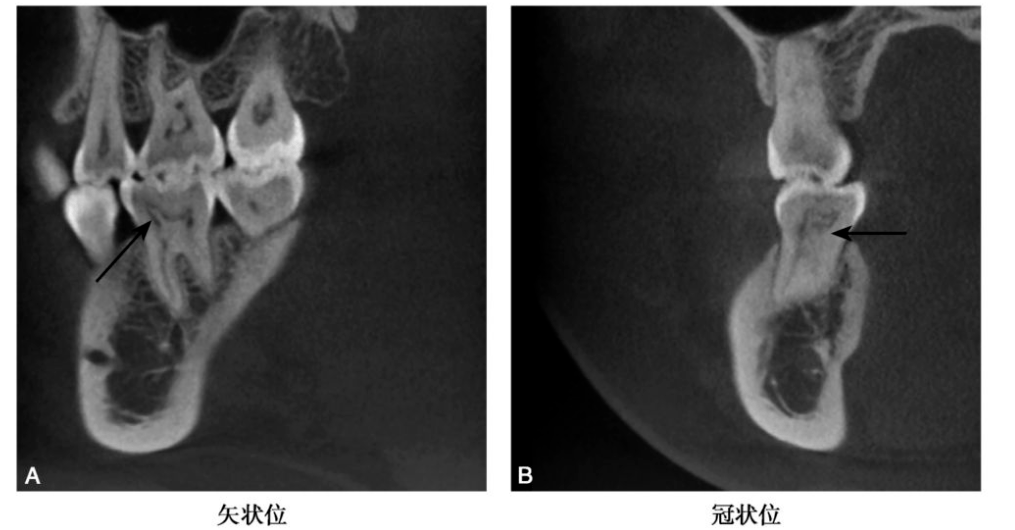

图2 B7髓腔髓石

CBCT示B7牙髓腔内可见高密度髓石影bccbch币,矢状位示呈卵圆形,水平位示呈针状(黑色箭头)

图3 C6髓腔髓石

CBCT示C6牙髓腔见高密度髓石影(黑色箭头),近中髓角髓石呈针状bccbch币。